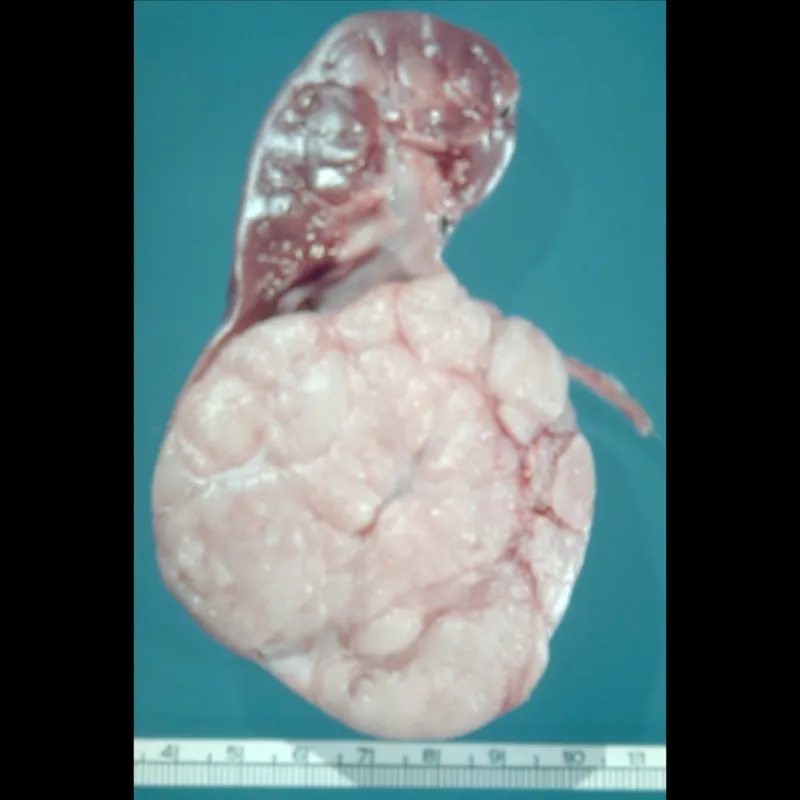

Wilms Tumor (Nephroblastoma)

- Most common pediatric renal tumor, typically ages 2-5.

- Presents as a large, palpable, unilateral flank mass; may cause hypertension.

- Histology: Triphasic (blastemal, stromal, epithelial).